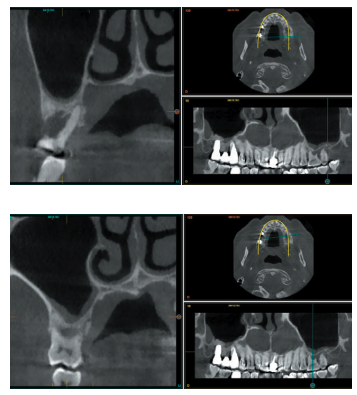

Todos los pacientes fueron tratados por un mismo cirujano, para la realización de la inserción de los implantes y la técnica de elevación transcrestal. Antes de la inserción de los implantes se utilizó una premedicación antibiótica consistente en amoxicilina 2gr vía oral una hora antes de la intervención y paracetamol 1 gramo vía oral (como analgésico). Posteriormente los pacientes prosiguieron con un tratamiento de amoxicilina 500-750 mg vía oral cada 8 horas (según peso) durante 5 días. Todos los pacientes fueron estudiados antes de la inserción de los implantes mediante modelos diagnósticos, exploración intraoral y realización de una tomografía computerizada de haz cónico (CBCT), analizado posteriormente mediante un software específico (BTI-Scan III). La cirugía se lleva a cabo mediante la técnica de fresado biológico descrita por nuestro grupo de estudio previamente, a bajas revoluciones, sin irrigación10, hasta ser finalmente completada mediante la elevación transcrestal con las fresas de corte frontal que se emplean también a bajas revoluciones. Una vez la membrana es accesible mediante la perforación crestal se despega mediante una ligera presión y se inserta el implante con el motor quirúrgico fijado a 25 Ncm y 25 rpm finalizando la inserción del implante con la llave dinamométrica. Todo el hueso recogido con las fresas se conserva en PRGF-Endoret fracción 2 sin activar, para posteriormente ser utilizado como injerto óseo particulado en la elevación, sin otros materiales accesorios9,12. Una vez finalizada la cirugía se realiza una radiografía periapical con paralelizador que será la que se utilice como punto de partida. Los pacientes acuden posteriormente para la realización de radiografías periapicales de control, tomadas con la misma técnica y sobre estas radiografías se realizan las mediciones necesarias para comprobar la estabilidad y pérdida ósea crestal de los implantes. La medición de la pérdida ósea marginal se realizó en la última radiografía periapical realizada con posicionador de seguimiento.

Una vez obtenida la radiografía en formato digital es calibrada mediante un software específico (Digora for Windows, SOREDEX Digital Imaging systems) a través de una longitud conocida en la radiografía como es el implante dental. Una vez se introduce la medida de calibración, el programa informático realiza un cálculo basado en esta medida para eliminar la magnificación, pudiendo realizar mediciones lineales exentas de este error. La pérdida ósea crestal fue medida en dos puntos: mesial y distal de cada implante. El implante fue la unidad de análisis para la estadística descriptiva en cuanto a la localización, dimensiones del implante, y mediciones radiográficas. La variable principal fue la supervivencia del implante y como variables secundarias se registraron la pérdida ósea mesial y distal. Fue realizado el test de Shapiro-Wilk sobre los datos obtenidos para verificar la distribución normal de la muestra. Las variables cualitativas se describieron mediante un análisis de frecuencias y las variables cuantitativas se describieron mediante la media y la desviación estándar. La supervivencia de los implantes se calculó mediante el método de Kaplan-Meier. Los datos fueron analizados con SPSS v15.0 para windows (SPSS Inc., Chicago, IL, USA).

En la Figura 2 se muestran los diámetros y longitudes de los implantes incluidos en el estudio en función de los milímetros de cresta ósea residual en altura. La densitometría media de la zona de inserción del implante del grupo fue de 293,33 HU (+/- 144,99). El torque medio de los implantes estudiados fue de 27,33 Ncm (+/- 16,99). Todos los implantes se cargaron en dos fases quirúrgicas y en todos se llevó a cabo una elevación de seno transcrestal con injerto óseo autólogo particulado obtenido del fresado, embebido en PRGF-Endoret como marterial de injerto. En ninguno de los casos se registraron complicaciones relativas a la cirugía. Los implantes presentaron un seguimiento medio de 13,33 meses tras la carga (+/- 3,09), no encontrándose complicaciones ni fracasos durante este tiempo de seguimiento, por lo que la supervivencia fue del 100%. Todos los implantes fueron rehabilitados mediante prótesis múltiple atornillada mediante elemento intermedio (transepitelial múltiple, Multi-im®), encontrándose dos de los implantes ferulizados a otros de la misma longitud (4,5 mm) y el resto a longitudes mayores. La ratio corona-implante medio para el grupo de estudio fue de 2,43 mm (+/-0,45). La pérdida ósea mesial final media de todos los implantes fue de 0,42 mm (+/- 0,51) y la pérdida ósea distal final media de 0,16 mm (+/-0,34). En las Figuras 3 –13 se muestra uno de los casos incluidos en el estudio.